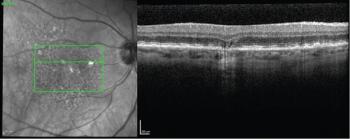

In a presentation at the Angiogenesis, Exudation, and Degeneration 2023 meeting hosted by Bascom Palmer Eye Institute, Baruch Kupperman, MD, PhD, detailed research in which investigators evaluated risuteganib for safety and effectiveness in patients with dry AMD.